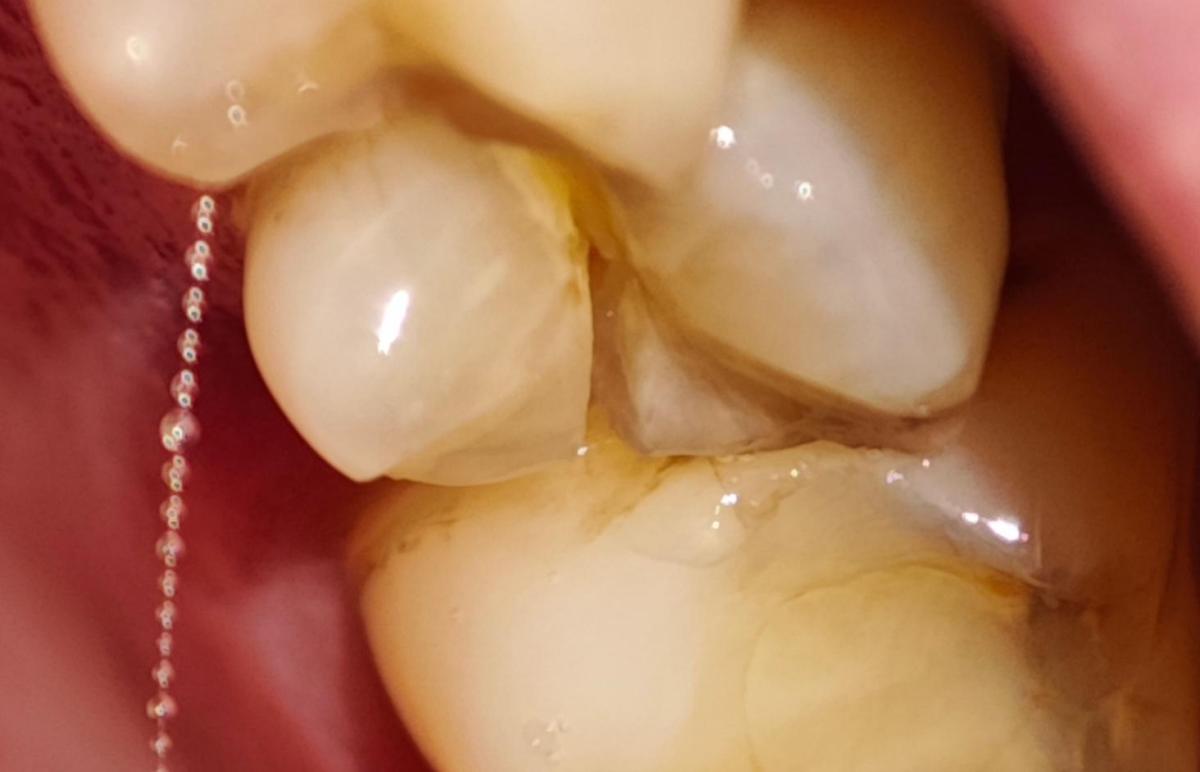

И буквально 2 дня назад, сидя смотря фильм, я почувствовал, как будто по зубу что-то ударило, сначала не придал значения, потом языком нащупал странность, зуб как будто стал шире и появилось что-то лишнее (не знаю, как правильно это выразить).

Ну и пошёл сделал фото под макросъёмкой, и увидел то, что его часть лопнула и он реально стал шире.